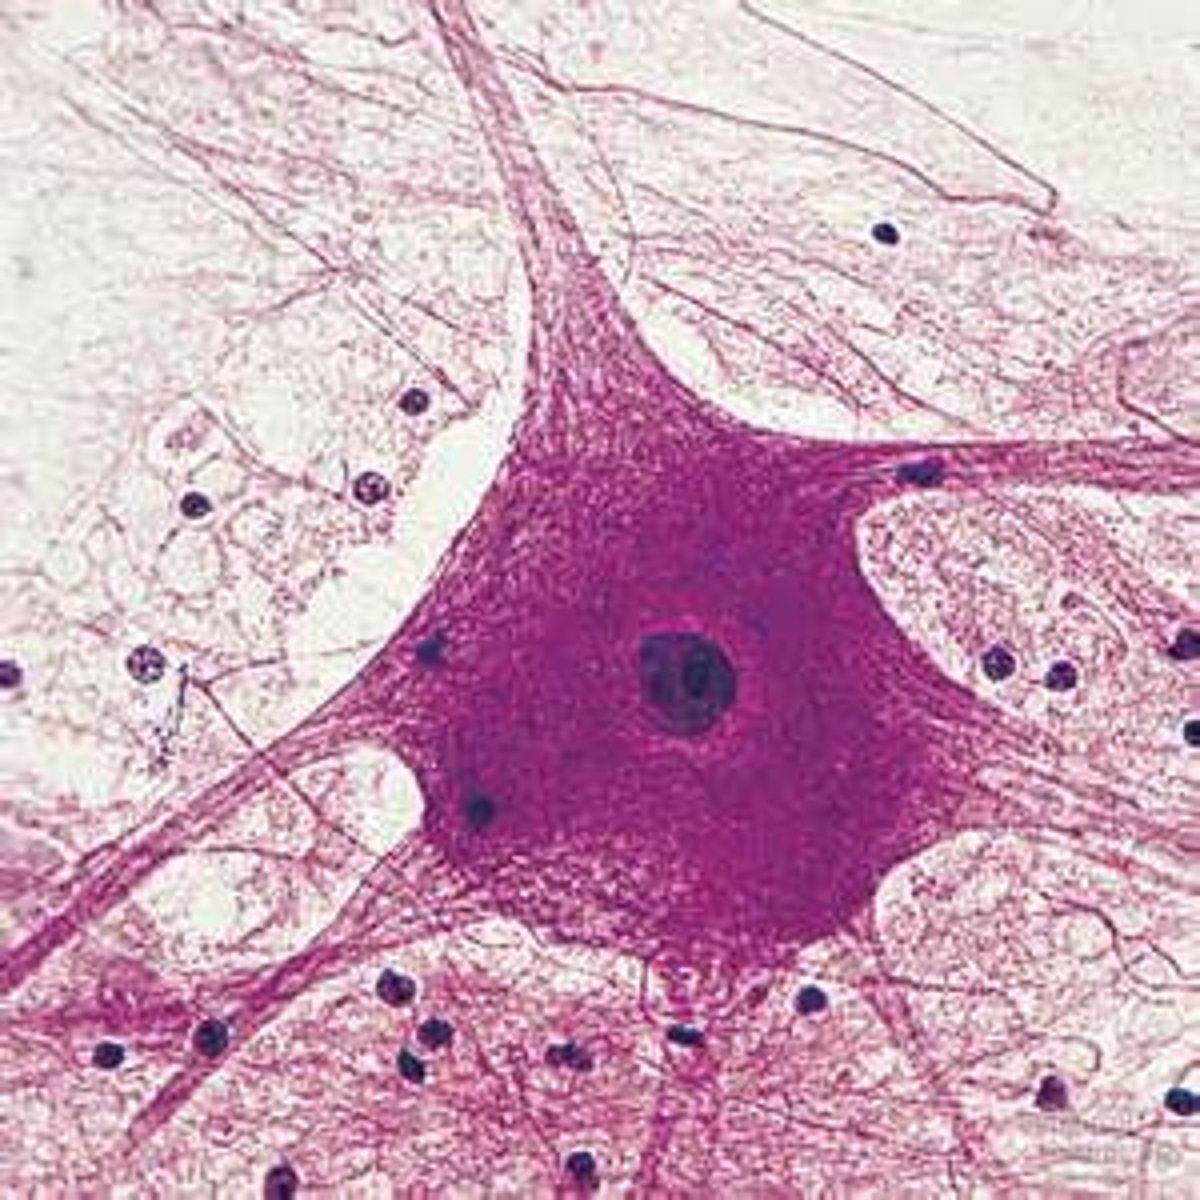

Cell

Basic unit of life